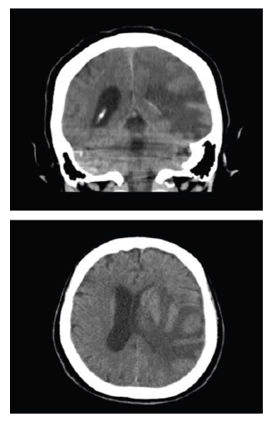

Extended studies, including neuroimaging, were ordered. A non-contrast cranial CT scan described a mass under study with left frontoparietal hypodensity, perilesional edema, and midline shift, suggesting a primary CNS lesion, probable GBM. An MRI with contrast was requested, which revealed a heterogeneous nodular lesion predominantly hyperintense on T2 and FLAIR sequences and hypointense on T1, with ring enhancement after intravenous contrast administration and hemosiderin signs on susceptibility-weighted imaging. The lesion measured approximately 41.7 × 40 × 36.5 mm (AP × T × L), associated with diffuse adjacent vasogenic edema, mass effect, and obliteration of the subarachnoid spaces. There was partial obliteration of the left lateral ventricle and approximately 8 mm midline shift to the right. Hyperintense images on T2 and FLAIR sequences were also observed in the periventricular and subcortical white matter of the bilateral frontal and parietal lobes, related to chronic microangiopathies. The conclusions were: (1) Left temporal space-occupying lesion, suggestive of high-grade glioma (glioblastoma multiforme); (2) Extensive vasogenic edema and local mass effect with subfalcine herniation. Neurosurgery considered that the patient required a left temporal tumor resection guided by neuro-navigation (Figure 1).

The patient remained in the intermediate care unit for 6 days in fair general condition, conscious, disoriented, with impaired judgment and reasoning, logorrhea, afebrile, without signs of systemic inflammatory response, awaiting scheduled surgical management. Supratentorial hemispheric tumor resection was performed through an osteoplastic craniotomy and temporal lobectomy of approximately 5 cm behind the temporal pole, oblique from T1 to T4, preserving the parahippocampal gyrus [5-7]. An intra-axial tumor lesion was found in the temporal lobe, friable and vascularized, which was resected within the lobectomy margins. Dural closure was achieved with a pericranial graft. Postoperatively, the patient persisted in the ICU with global disorientation, incoherent, fluent speech, and sensory aphasia (Figure 2).

XXXXXXXX

Figure 2: Brain MRI with contrast.